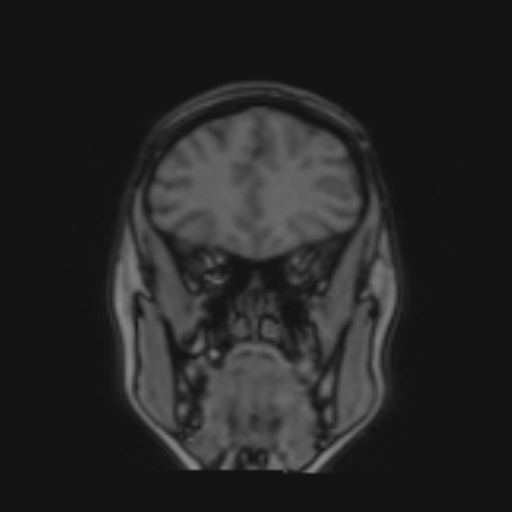

Identificativo:

Descrizione Serie: t2_tse_cor